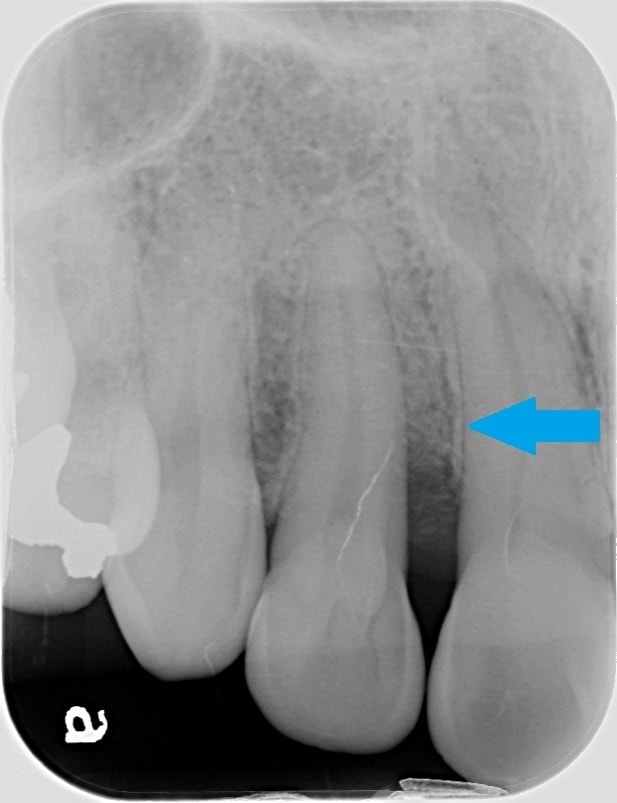

治療前は、赤の矢印で示すように歯の周りに黒いところがあることが分かるかと思います。簡単に言うと、骨が溶けた状態になります。

通常、歯周ポケットと呼ばれる歯と歯茎の間の溝は3㎜程度なのですが、10㎜を超える歯周ポケットがありました。CTは、手術前に骨の欠損形態を的確に把握できるため、歯周病の治療にも非常に有用です。

歯周病の基本的な治療を行い、その後に、歯周組織再生療法という失われた歯の周りの組織を再生させる手術を行って約2年のレントゲンになります。

青の矢印で示すように、治療前黒かった部分が、白くなってきていることが分かるかと思います。失われた歯周組織の再生が促されていることが推測されます。CTにおいても歯の周囲の失われた骨が再生してきていることが、分かるかと思います。